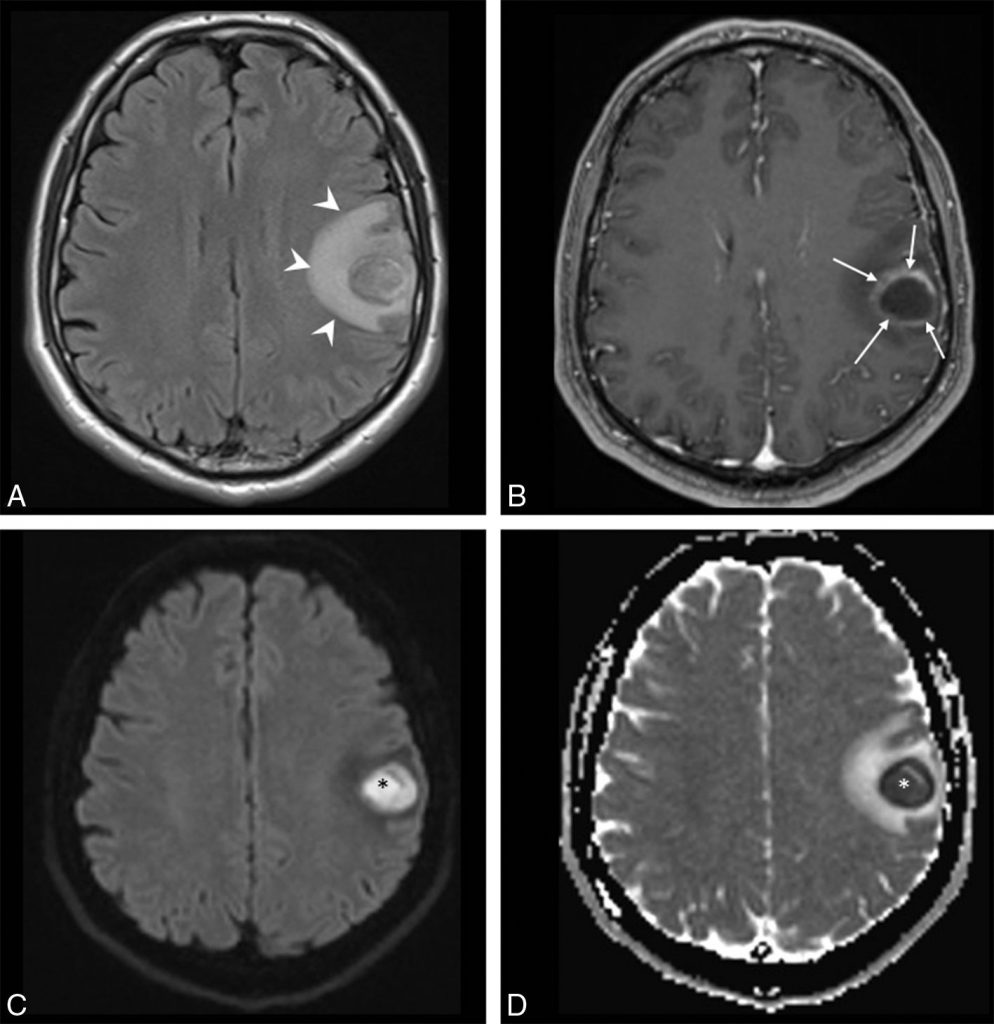

Fig. 49.1. Abcès cérébral à pyogènes. IRM cérébrale.

Coupes axiales en FLAIR (A), en T1 avec injection de gadolinium (B), en diffusion (C) avec cartographie du coefficient apparent de diffusion (ADC) (D). Collection intracérébrale frontale gauche en hyposignal en T1 limitée par une paroi prenant fortement le contraste (flèches), œdème périlésionnel étendu de la substance blanche en hyposignal en T1 et en hypersignal en FLAIR (têtes de flèches). Hypersignal en diffusion avec ADC diminué caractéristique d’un abcès à pyogènes (∗).

Source : CERF, CNEBMN, 2022.

L’IRM doit comporter des séquences pondérées en FLAIR, en T1 sans et avec injection de gadolinium ainsi qu’une séquence de diffusion, très spécifique pour le diagnostic d’abcès à pyogènes (figure 49.1).

- En cas d’abcès à pyogènes : centre nécrotique en hypersignal sur la séquence en diffusion traduisant un milieu très visqueux. Cet aspect en diffusion est caractéristique des abcès à pyogènes et n’est pas retrouvé dans les autres types d’abcès comme les abcès parasitaires (toxoplasmose) ni dans les tumeurs nécrotiques.

- Prise de contraste intense (en scanner et en IRM) des parois de l’abcès.

- Hypersignal caractéristique en diffusion du centre des abcès à pyogènes.